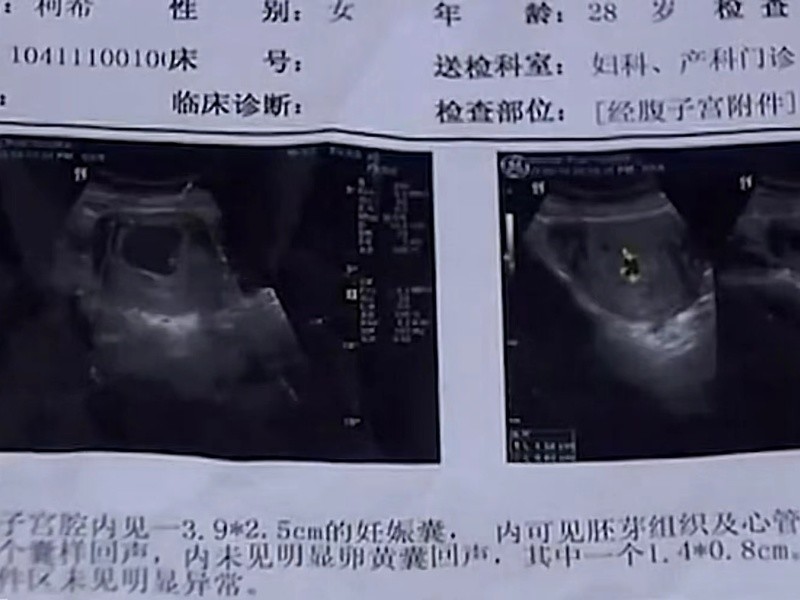

2015年初,28岁的柯希感到身体不适,刚开始以为干活累着了,可是一连好几天症状都没减轻,丈夫担心地劝她到医院做个检查。

不查不要紧,当检查结果出来时,可把全家人高兴坏了——柯希怀孕了!不只是怀孕,而且还是双胞胎,这突如其来的喜讯,让柯希一家都激动不已。